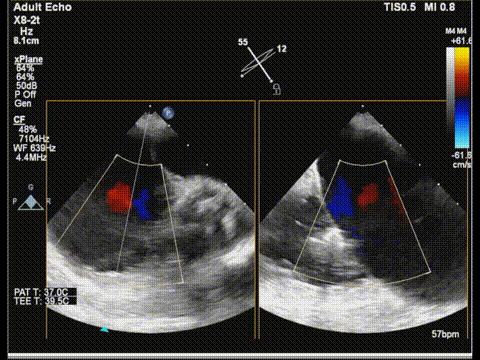

术前食道超声:

房颤,瓣环扩大的房性二尖瓣反流,反流主要集中在二区,二区后叶部分脱垂,后叶的长度16mm,前叶的长度是37mm。房间隔整体的条件可,从瓣环到拟定的卵圆窝顶部高度大概是41mm。

二尖瓣2区

二尖瓣2区color